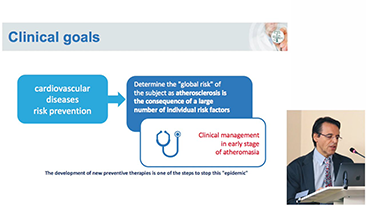

Covid-19 - Pr├│ba si? dla ludzi i aparatury

W zwi?zku z pandemi? koronawirusa szpitale i personel medyczny opracowa?y nowe praktyki robocze obejmuj?ce post?powanie w sytuacjach dotycz?cych stanów ostrych, dystans spo?eczny, rygorystyczne stosowanie ?rodków ochrony indywidualnej (?OI), mycie r?k i codzienn? dezynfekcj? sprz?tu. Dodatkowo w punktach opieki medycznej coraz wi?ksze znaczenie zacz?? mie? przeno?ny, wysoce mobilny i wszechstronny sprz?t, przydatny zw?aszcza w sytuacji, gdy oddzia?y i bloki operacyjne s? rozmieszczone na kilku pi?trach, a dost?p do specjalistycznych urz?dzeń jest ograniczony.